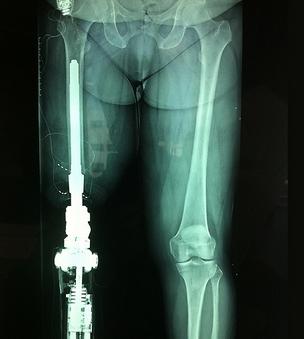

在中國,需要假肢醫(yī)療設(shè)備的人有很多,但是傳統(tǒng)假肢造價(jià)高,還容易引起并發(fā)癥,導(dǎo)致這一需求長時(shí)間得不到完善的解決。好在近些